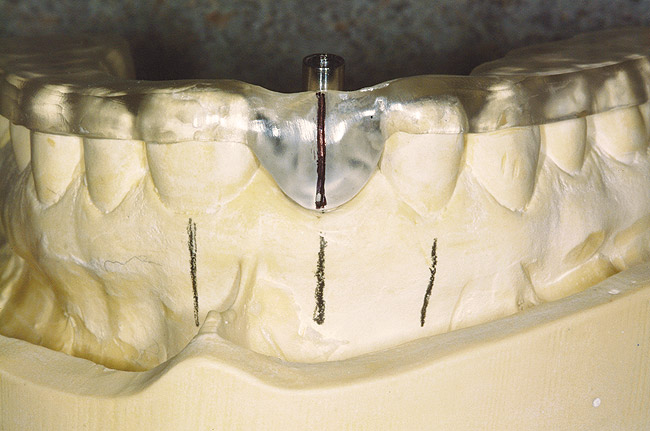

A set of mounted casts in centric relation with a full-contour diagnostic wax-up, including the hard- and soft-tissue deficits, is mandatory prior to initiating treatment. This is beneficial in accessing the edentulous space and communicating the information concerning the edentulous defect with the laboratory technician, the implant surgeon, and most importantly, the patient. In addition, CBCT can also be extremely helpful in diagnosing the edentulous site 3-dimensionally and providing vital information to the surgeon prior to implant placement (Figure 9). Only after the diagnosis and treatment plan is fully understood by all parties should the treatment be initiated. In many situations, hard- and soft-tissue grafts are necessary in order to reconstruct the edentulous site as near to its original contours as possible (Figure 10, Figure 11 and Figure 12). This will significantly enhance proper positioning of the implant for prosthetic needs and help to increase the prognosis for an esthetic result.27 At the time of implant placement, a surgical template should be used to help ensure that the implant is placed in the proper position. The surgical template can be fabricated from the diagnostic wax-up or generated from planning software using the Digital Imaging and Communications in Medicine (DICOM) data obtained from the CBCT. The esthetic result is generally dictated at the time the implant is placed, hence the need for such a detailed assessment (Figure 13, Figure 14, Figure 15 and Figure 16).

Figure 10  Preparing the osteotomies using a surgical template.

Figure 10